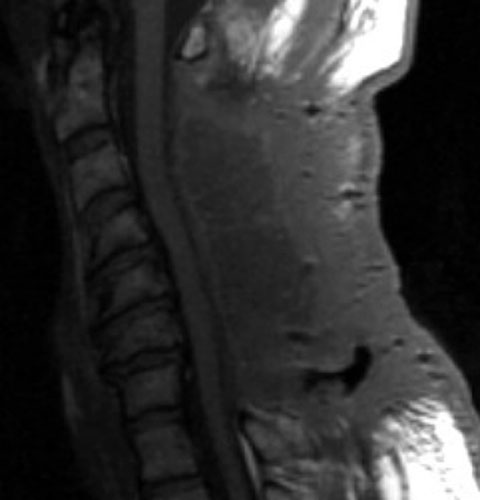

Seroma and Epidural Scar